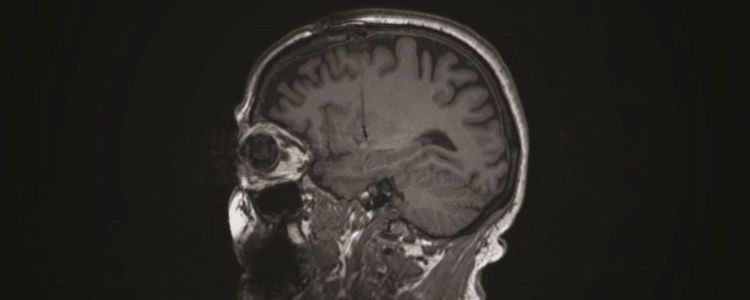

Новозеландська біотехнологічна компанія Living Cell Technologies розробила лікування хвороби Паркінсона з використанням клітин судинного сплетення свиней. Ці клітини знаходяться в області мозку, яка виробляє суміш сигнальних молекул і чинників зростання, які підтримують здоров'я нервів, тому дослідники пересадили здорові клітини від донорів свині на чотири людини. Через 18 місяців після операції результати все ще багатообіцяючі, тому дослідники почали плацебо-контрольоване дослідження у 18 додаткових пацієнтів в травні.

Хвороба Паркінсона характеризується прогресуючою втратою клітин, що продукують допамін. Сам допамін допомагає контролювати мозок в організмі. Метою цього лікування є накопичення існуючих здорових клітин головного мозку у реципієнтів для уповільнення або запобігання подальших втрат. До сих пір цей метод виявився успішним в лікуванні щурів з видоспецифічні наслідком хвороби Паркінсона.